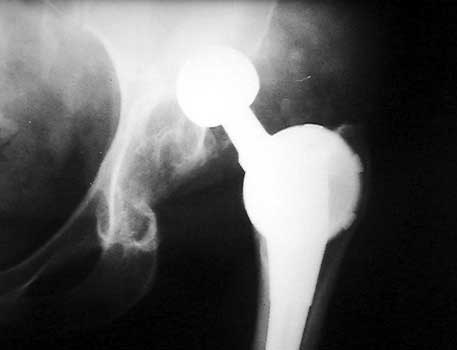

Dislocated femoral component related to non union of greater

trochanteric osteotomy. Post operative radiograph with constraining ring about

femoral head, which helps maintain head in cup. Greater trochanter resected.